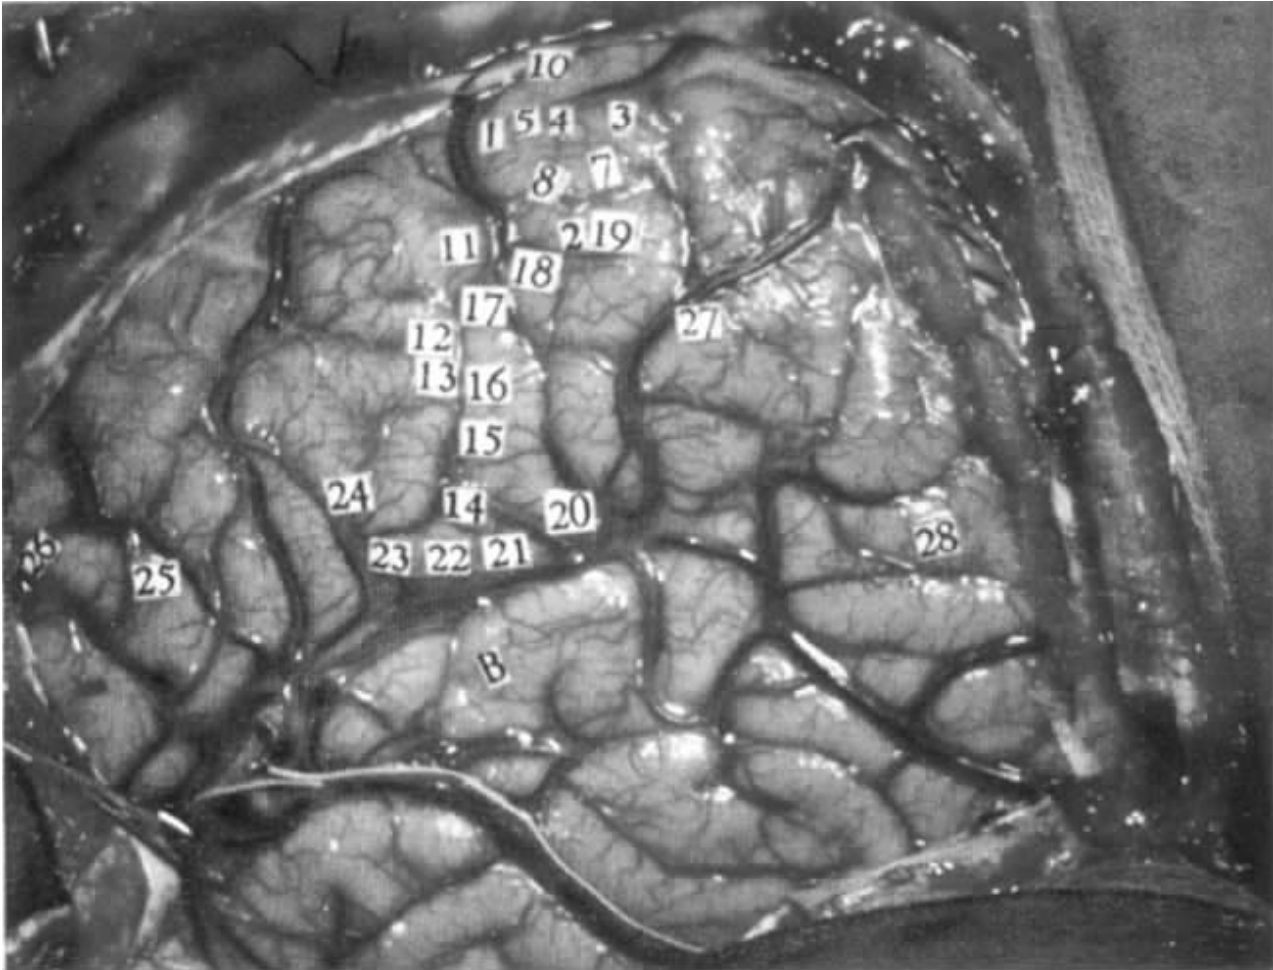

病例1 C.H.(为局灶性脑癫痫,有不自主动作及咀嚼行为)

在局麻下行左侧开颅术。

电刺激部位

左脑,中央沟区及语言区(图6-1)。

电刺激脑的反应及特点

8 小指的感觉。

18 右下唇外面的感觉。

17 右下唇内面的感觉。

16 舌右侧末端的麻刺感。

12 下颚颤动。

13 下颚转向右边。

图6-1 病例C.H.左大脑半球(数字标签1至24所对应的是中央沟的运动和感觉反应,颞叶上的白线是将要切除的皮质界限,刺激点26、27、28使患者失语)

23 (讲话停顿)当病人讲话时刺激,病人停止讲话,后来他观察到他已经不能讲话。当病人不讲话时重复刺激,没有观察到异常。

24 (讲话停顿)病人试图讲话,嘴巴移向右侧,但没有发出声音。

25 要求病人命名图片,在病人命名时刺激。病人短时迟疑,然后成功地命名“蝴蝶”。

刺激24和25之间没有打断命名。

26 (失语)病人说:“我知道是什么。那是放进你鞋子里的东西。”当刺激停止,他说:“脚。”点26位于25之前。

前面刺激电压为2V,下述刺激电压加大到3V。

27 病人不能命名。他说:“我知道它是什么。”当刺激撤去,他立刻说:“树。”

28 病人不能命名。当刺激撤去,他仍不能命名。当被问及,他说:“不行。”大脑皮层电图记录表明有后放电,扩展到整个颞叶。在这个过程中,病人仍然不能命名物体,他不再回答。当电记录显示出放电结束,病人就马上开始说话:“现在我能说了——蝴蝶。”当问他之前为什么不能命名图片时,他说:“我不能找到‘蝴蝶’一词,后来我试着找到了‘蛾’这个词。”

病人的左侧颞叶下表面找到了一块创伤性疤痕。脑皮层电图显示这个区域放电。颞叶前部被切除。手术后18小时,他仍能讲话,但是接着他失语,并持续了2周。